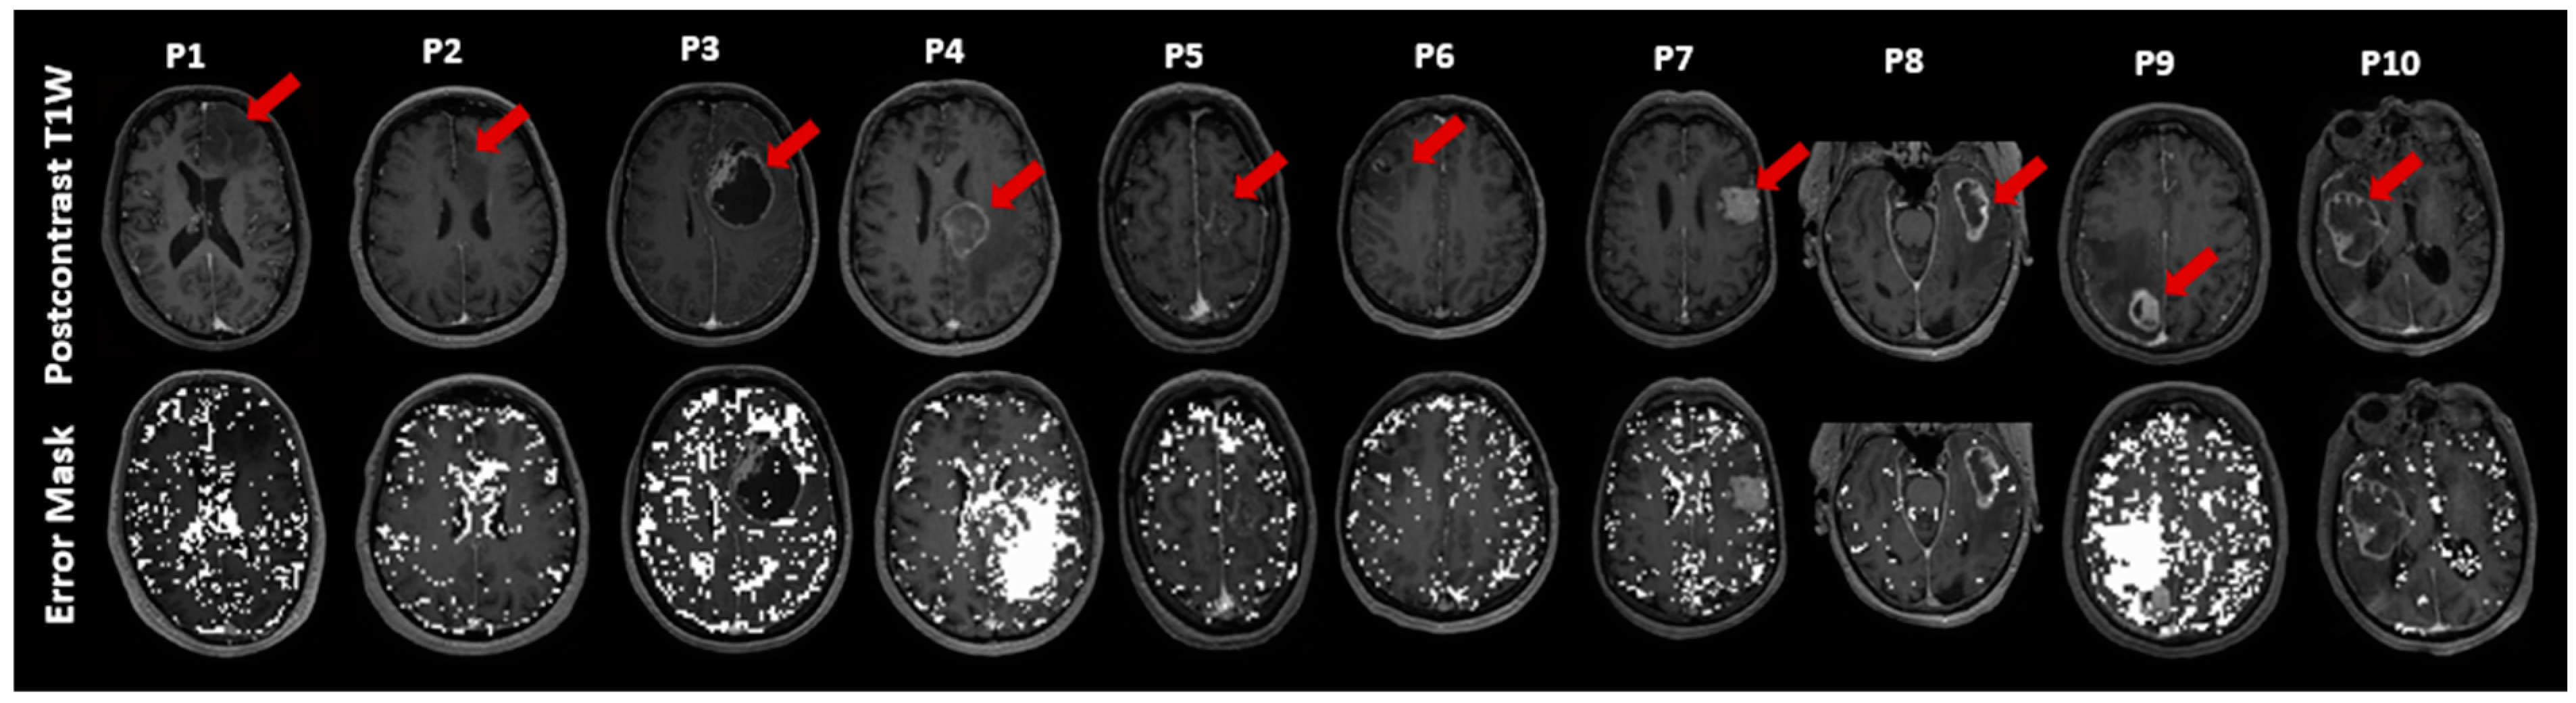

3.1. Patient and Biopsy Characteristics

| Patient No./Sex/Age(y) | Pathologic Diagnosis | # Samples from Necrosis VOI | # Samples from Enhancing VOI | # Samples from Nonenhancing VOI |

|---|---|---|---|---|

| 1/M/56 | Oligodendroglioma (grade 2) | - | - | 4 |

| 2/F/74 | Astrocytoma (grade 2) | - | - | 4 |

| 3/F/52 | Brain Metastasis (lung carcinoma) | - | 2 | - |

| 4/M/57 | Brain Metastasis (adenocarcinoma) | 2 | 1 | - |

| 5/M/72 | Brain Metastasis (adenocarcinoma) | - | - | 2 |

| 6/F/40 | Oligodendroglioma (grade 3) | - | 2 | 1 |

| 7/F/78 | Brain Metastasis (adenocarcinoma) | - | 3 | - |

| 8/M/75 | Glioblastoma (grade 4) | 3 | 1 | - |

| 9/F/68 | Brain Metastasis (melanoma) | 1 | 3 | - |

| 10/M/75 | Glioblastoma (grade 4) | 2 | 2 | - |

| Total: 8 | Total: 14 | Total: 11 |